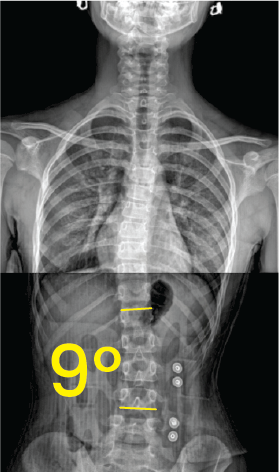

Göğüs ve bel bölgesinde 20 derece eğimli skolyozu gösteren X-ışını omurga röntgeni.Göğüs ve karın bölgesinin röntgeni üzerinde, omurga eğriliğini vurgulayan 9 derece açıyla işaretlenmiş omurga escoliosis görüntüsü.